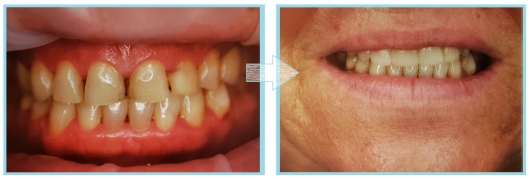

Jestem Amerykaninem, ale mieszkam w Polsce ponad 10 lat. Zajmuję się zachowawczą, leczeniem kanałowym pierwotnym i wtórnym pod mikroskopem, protetyką i prostą chirurgią. Wykonuję też Bonding i Flow Injection Technique.